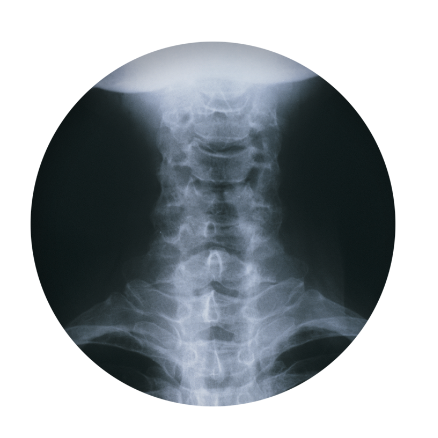

허리디스크를 정확하게 진단하기 위해서는 엑스레이로는 힘들며, MRI를 통해 검사해야 정확하게 볼 수 있습니다.

MRI가 몸에 좋지 않지만 허리 통증으로 엑스레이만 진행 할 경우 오진이 많아 지속적인 통증이 계속 된다면 허리디스크를 의심하고 MRI 검사를 한번 받아보시길 권유드립니다.